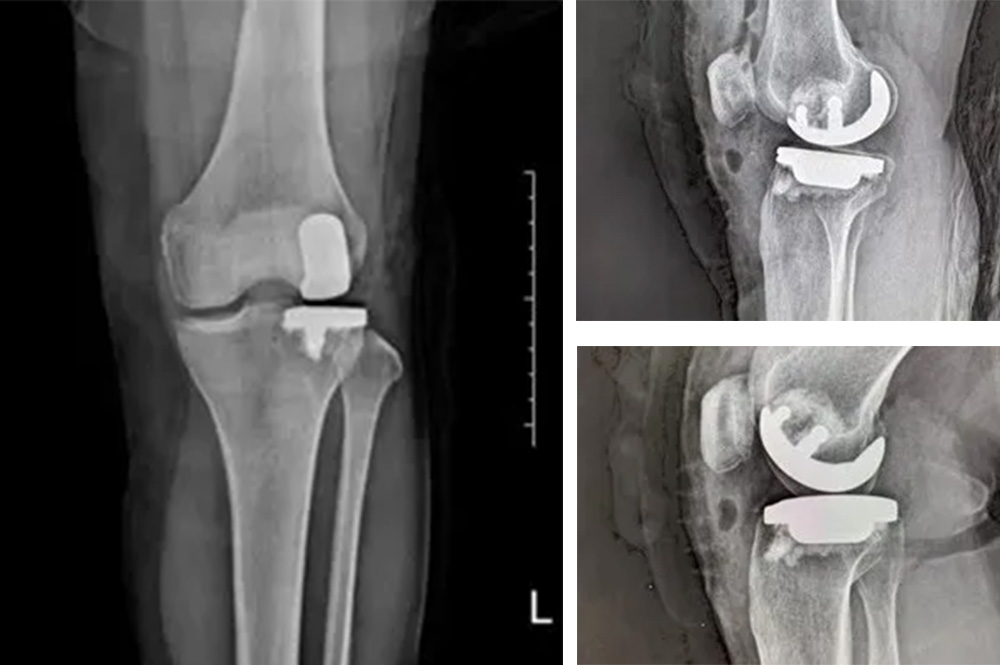

經(jīng)過(guò)詳細(xì)的體格檢查、影像學(xué)評(píng)估和三維重建,醫(yī)療團(tuán)隊(duì)確認(rèn)鮑奶奶的情況非常適合進(jìn)行膝外側(cè)單髁置換術(shù)。這種微創(chuàng)手術(shù)創(chuàng)傷小、恢復(fù)快,能夠最大程度保留膝關(guān)節(jié)的自然結(jié)構(gòu)和功能。

手術(shù)當(dāng)天,骨科團(tuán)隊(duì)采用微創(chuàng)切口,僅約8厘米,遠(yuǎn)小于傳統(tǒng)全膝關(guān)節(jié)置換手術(shù)切口。術(shù)中精準(zhǔn)定位,僅置換病變的膝關(guān)節(jié)外側(cè)間室。

手術(shù)使用了最新的單髁假體系統(tǒng),這種假體設(shè)計(jì)更符合人體工程學(xué),能夠更好地恢復(fù)膝關(guān)節(jié)的自然運(yùn)動(dòng)軌跡。